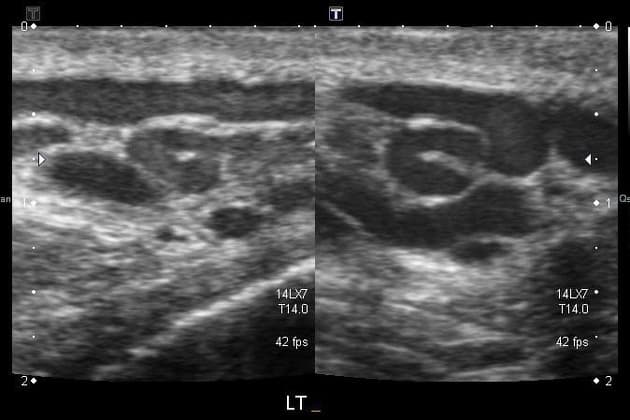

- •Scrotal ultrasound with Doppler

A varicocele is an abnormal enlargement of the pampiniform venous plexus in the scrotum, similar to varicose veins in the legs. These dilated veins allow warm blood to pool in the scrotum, increasing testicular temperature and exposing sperm to toxins from refluxing blood.

- •Visible or palpable "bag of worms" in scrotum